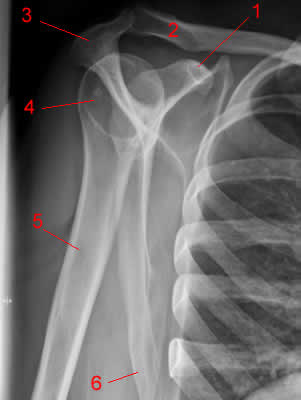

Это головка плечевой кости в ортопроекции.

Так, для интересу.

Область плечевого сустава.

Рис. 2. 1, клювовидный отросток;. 2, Ключица. 3, Акромион. 4, головка плечевой кости. 5, плечевая кость. 6, латеральный край лопатки.

+1